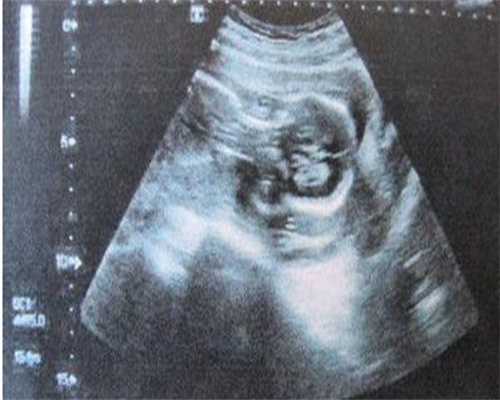

总的来说,醋酸甲羟孕酮片功效和作用有很多,但需要在医生指导下服用,醋酸甲羟孕酮片的剂量及用法有严格要求,在用药之前通常需要做B超检查及血常规检查,从而了解子宫内膜的厚度及是否贫血等。